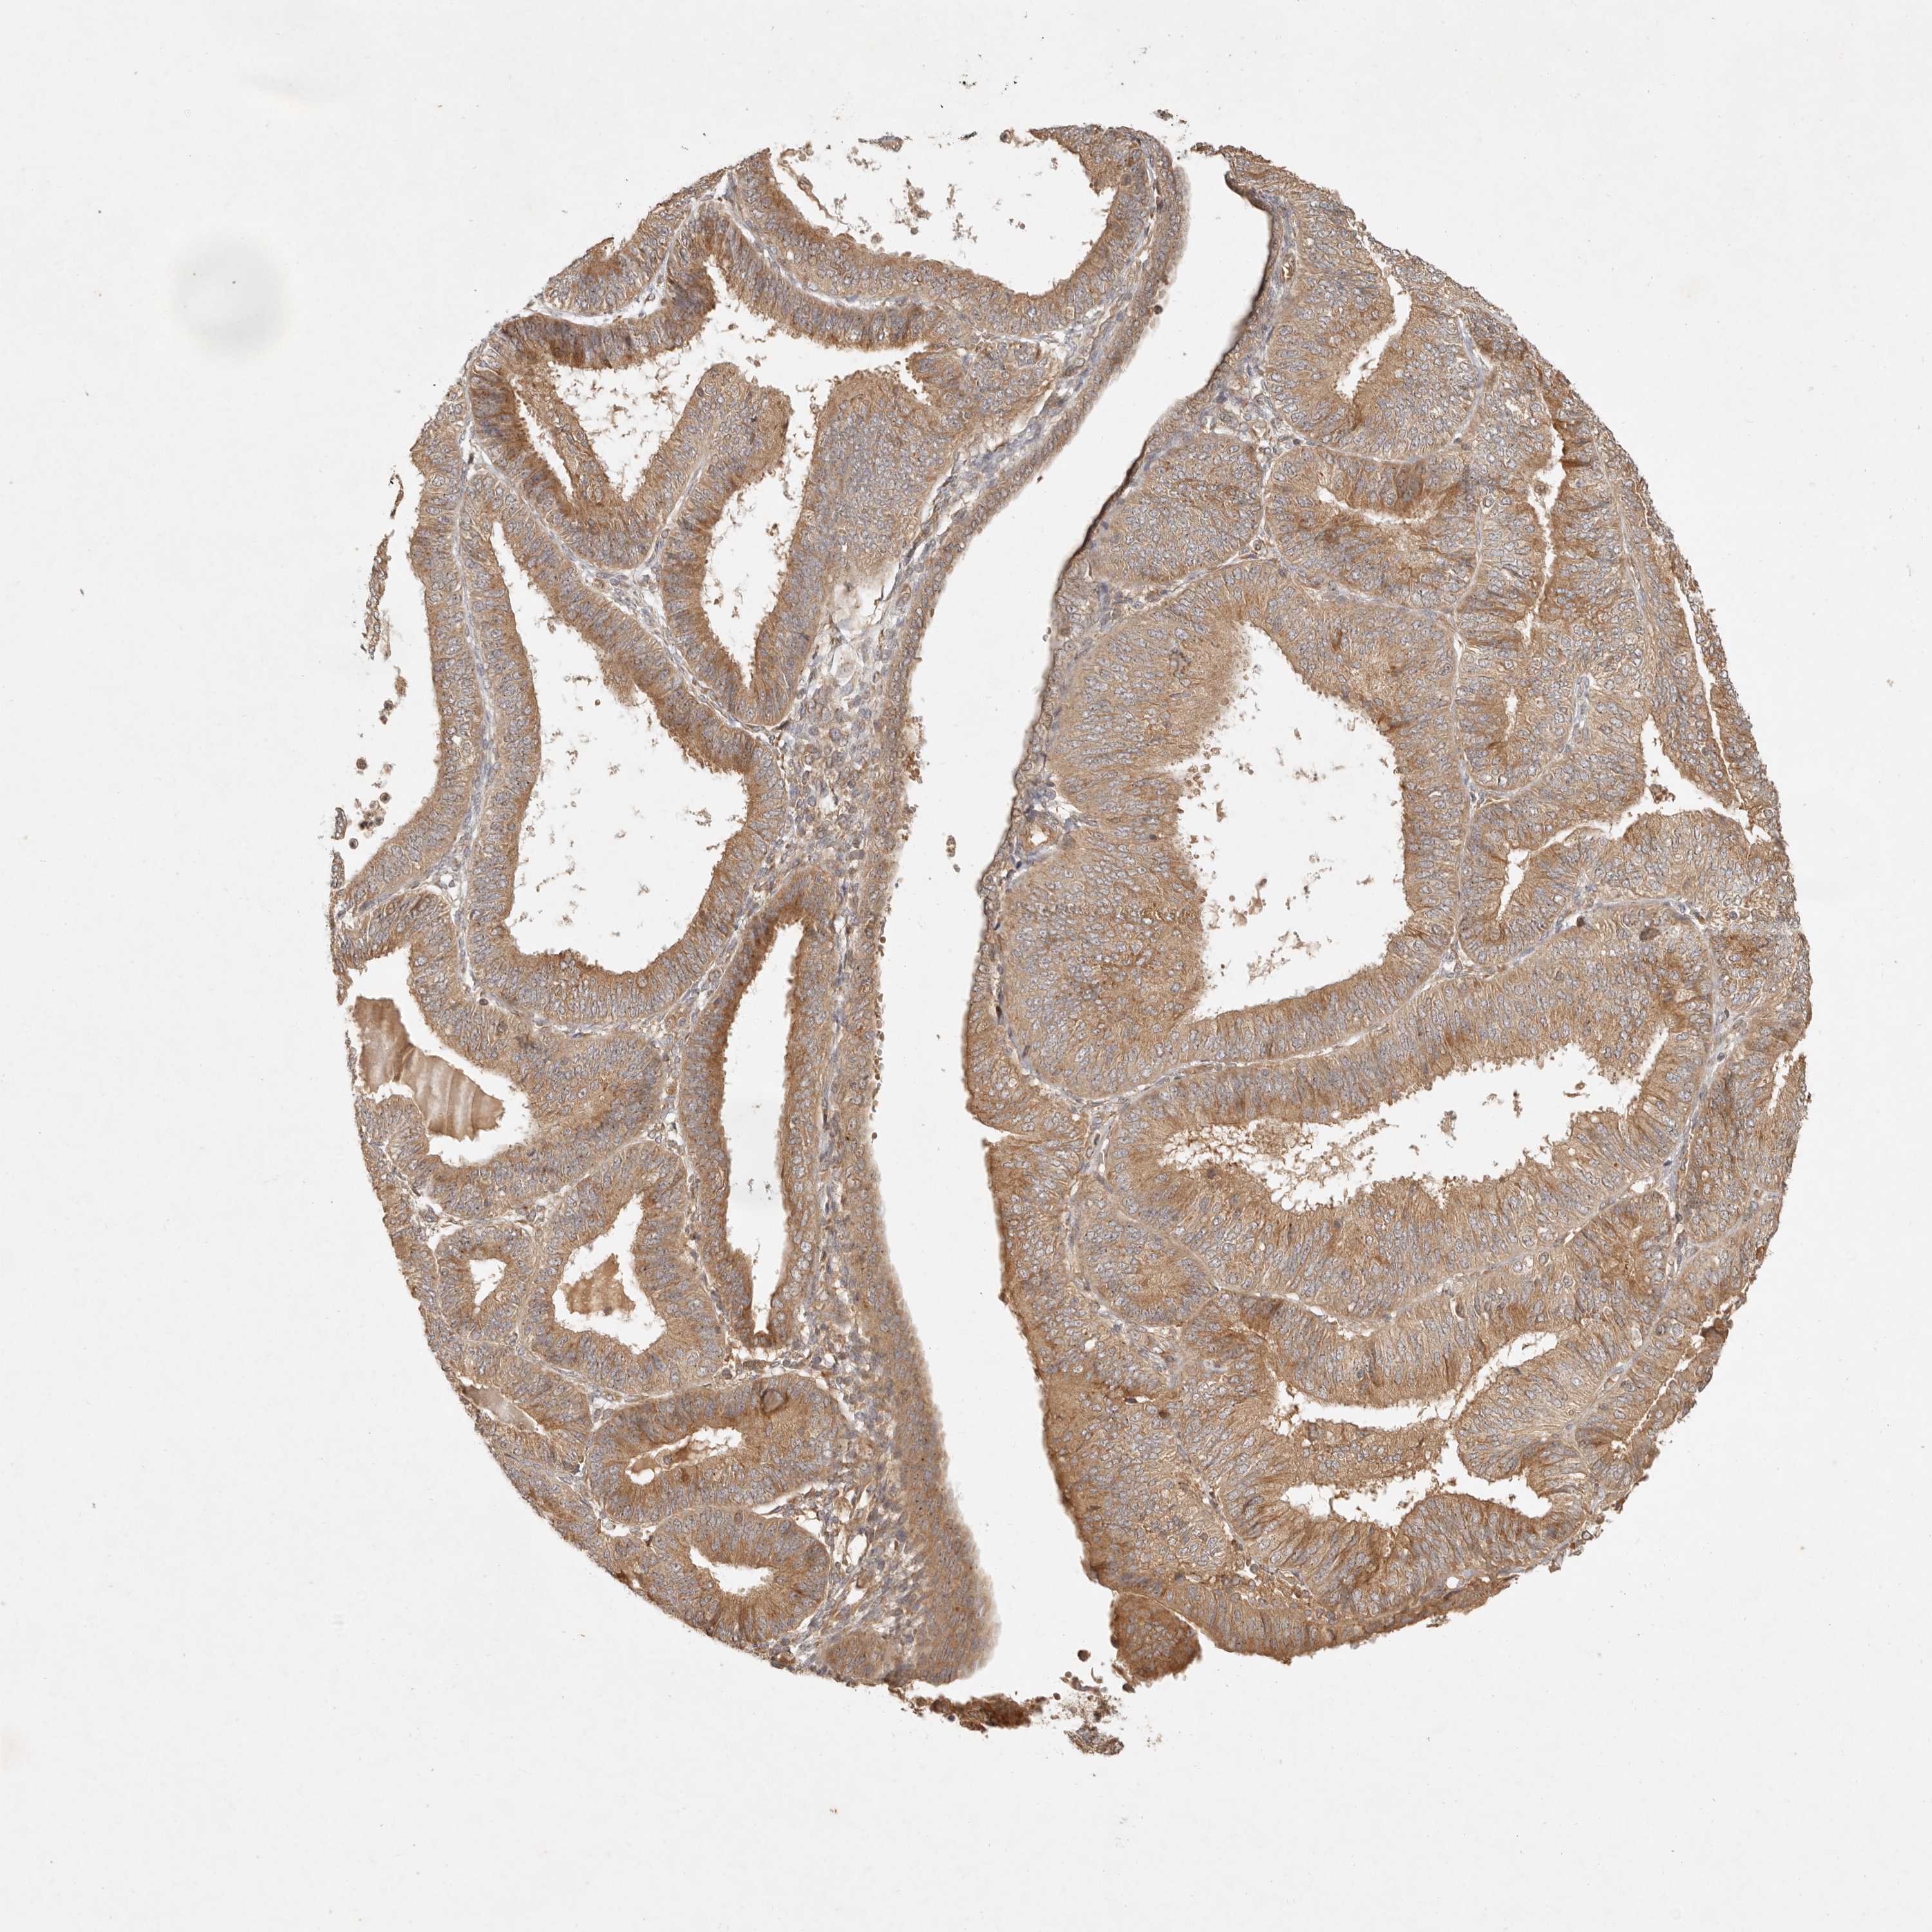

ENDOMETRIAL CANCER - Protein expressioni

A mouse-over function shows sample information and annotation data. Click on an image to view it in a full screen mode. Samples can be filtered based on level of antibody staining by selecting one or several of the following categories: high, medium, low and not detected. The assay and annotation is described here.

Note that samples used for immunohistochemistry by the Human Protein Atlas do not correspond to samples in the TCGA dataset.

Antibody stainingi

Antibody staining in the annotated cell types in the current human tissue is reported as not detected, low, medium, or high, based on conventional immunohistochemistry profiling in selected tissues. This score is based on the combination of the staining intensity and fraction of stained cells.

Each image is clickable and will lead to virtual microscopy that enables deeper exploration of all samples and also displays staining intensity scores, fraction scores and subcellular localization as well as patient and tissue information for each sample.

Antibody HPA029511

Staining

High

Medium

Low

Not detected

Intensity

Strong

Moderate

Weak

Negative

Quantity

>75%

75%-25%

<25%

None

Location

Nuclear

Cytoplasmic/membranous

Cytoplasmic/membranous,nuclear

Adenocarcinoma, NOS

Adenocarcinoma, metastatic, NOS